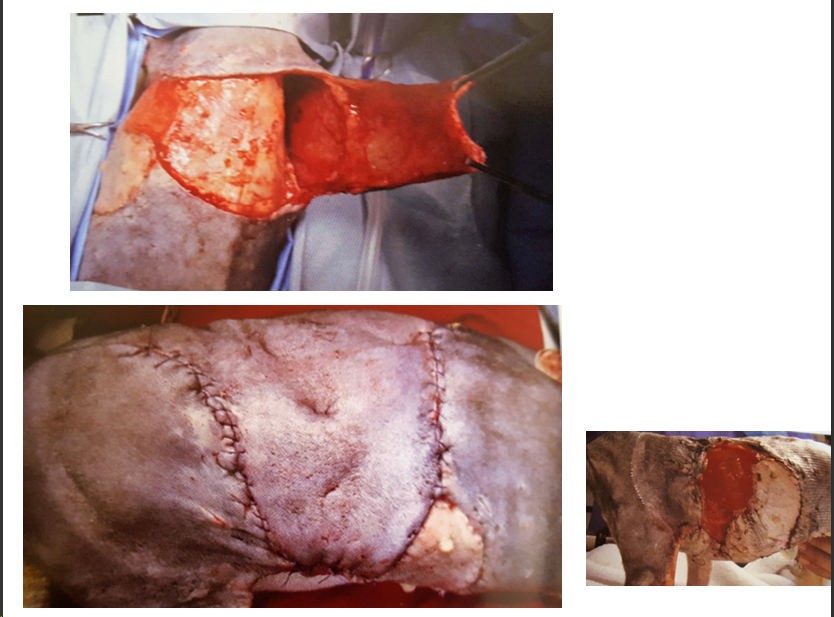

“Herida por jabalí — transformación de la herida en un defecto cuadrado.”

“Herida por mordedura.”